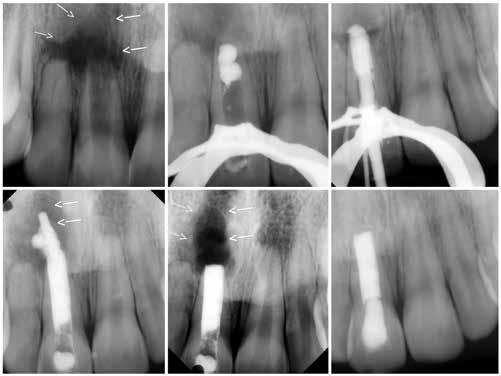

#13, #14 for ridge preservation. At a later date, three implant-supported crowns in close proximity were placed in these sites. Notably, the crowns were non-splinted. (Fig. 1).

In July 2021, the patient presented with mobile implants #12, #13 and #14 to his dental practitioner (Fig. 2). The implants were removed without bone grafting.

The patient received an interim removable partial denture and presented to the oral surgery clinic for evaluation for a fixed solution. At the time of initial consultation (September 2021), it was determined that failure of the implants was due in part to excessive occlusal forces as well as lack of proper hygiene maintenance and recall by the patient. For success, prior restoration design should have minimized difficult-to-reach areas for brushing

Fig. 1: May 2021. Panoramic radiograph shortly after placement of upper left #12, #13, #14.